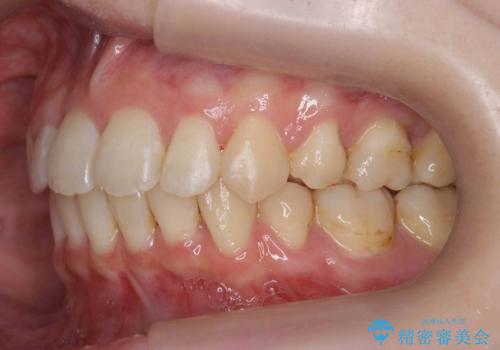

左上の小臼歯が込み合っており、虫歯治療が厳しい状態でした。

矯正治療をおすすめし、ちょうど虫歯がひどい歯は抜歯して前歯を下げました。

下顎の大臼歯が前に倒れこんでいたため、矯正用ミニスクリューで後ろに起こしています。